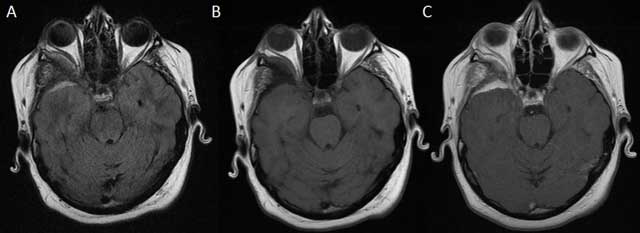

Figure 2

MRI of the brain with axial FLAIR (A) and unenhanced and contrast-enhanced axial T1-weighted images (B, C) shows right-sided anterotemporal FLAIR-hyperintense contrast-enhancing dural thickening abutting the bony sphenoid changes.